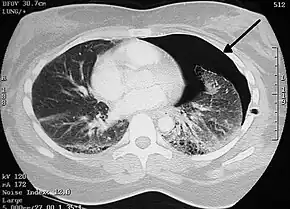

A chest tube is a flexible plastic tube that is inserted through the chest wall into the pleural space.[1] It is used to remove air (pneumothorax), fluid (pleural effusion, hemothorax), or pus (empyema).[1] In those with a tension pneumothorax, a needle thoracostomy may be carried out first.[1]

In a pneumothorax bubbles will be seen in the drainage system.[2] A chest X-ray is than carried out to confirm placement.[2] Antibiotics are often given to prevent infection.[3] The tube may be removed once air leakage has stopped for more than 12 to 24 hours or the amount of fluid out is under 200 ml per 24 hours.[2] Removal should occur when the person has taken and is holding a maximal breath.[2] Another chest X-rays is done after 12 to 24 hours.[2] Complications may include subcutaneous emphysema, blockage of the tube, bleeding, infection, reexpansion pulmonary edema, and lung or diaphragm injury.[1]